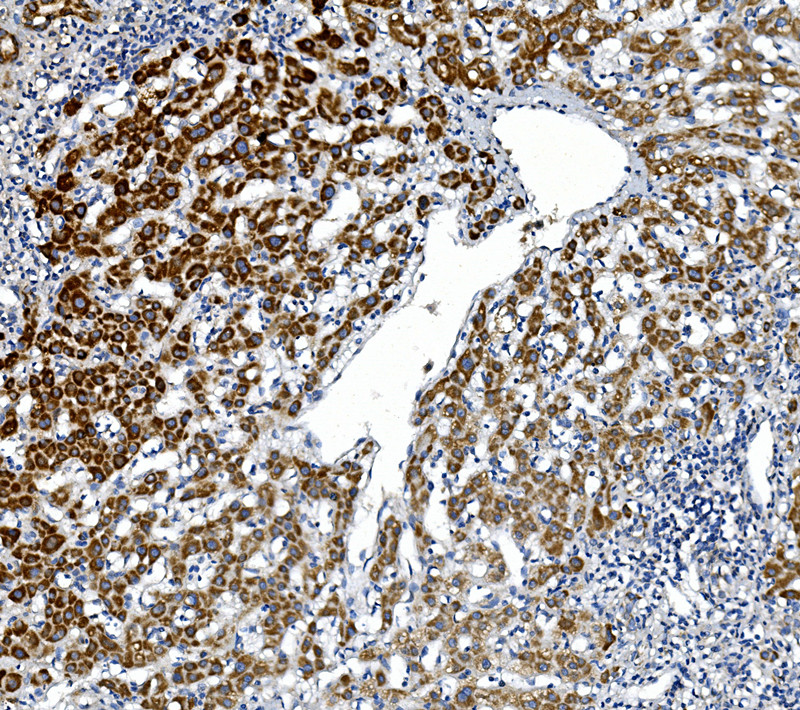

IHC analysis of GPNMB using anti-GPNMB antibody (A02439-1).

GPNMB was detected in a paraffin-embedded section of human liver cancer tissue. Biotinylated goat anti-rabbit IgG was used as secondary antibody. The tissue section was incubated with rabbit anti-GPNMB Antibody (A02439-1) at a dilution of 1:200 and developed using Strepavidin-Biotin-Complex (SABC) (Catalog # SA1022) with DAB (Catalog # AR1027) as the chromogen.